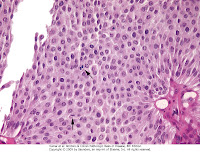

- Los canceres uroteliales papilares de alto grado contienen células que pueden mostrar uniones imperfectas y núcleos hipercromaticos grandes. Es frecuente encontrar figuras mitóticas, atípicas: Existe una desorganización y perdida de polaridad. Tienen mayor incidencia de invasión de la capa muscular, y un gran potencial metastásico.

Los tumores agresivos se pueden extender no solo hacia la pared vesical si no en estadios mas avanzados pueden invadir la próstata, vesículas seminales ureteres y retroperitoneo. Puede producirse una diseminación hematógena hacia el hígado, pulmones y médula osea.- El carcinoma in situ, presenta células citologicamente malignas dentro del urotelio plano. Varia desde una atipía de todo el espesor a células malignas dispersas en un urotelio que normal (diseminación pagetoide). Hay ausencia de cohesividad, lo que facilita la diseminación hacia la orina. Aparece macroscopicamente como un área de enrojecimiento, granularidad o engrosamiento de la mucosa sin una masa intraluminal evidente. Normalmente es multifocal extendiéndose también a los uréteres u uretra. Mas del 50% pueden progresar a un cáncer que invade la muscular.